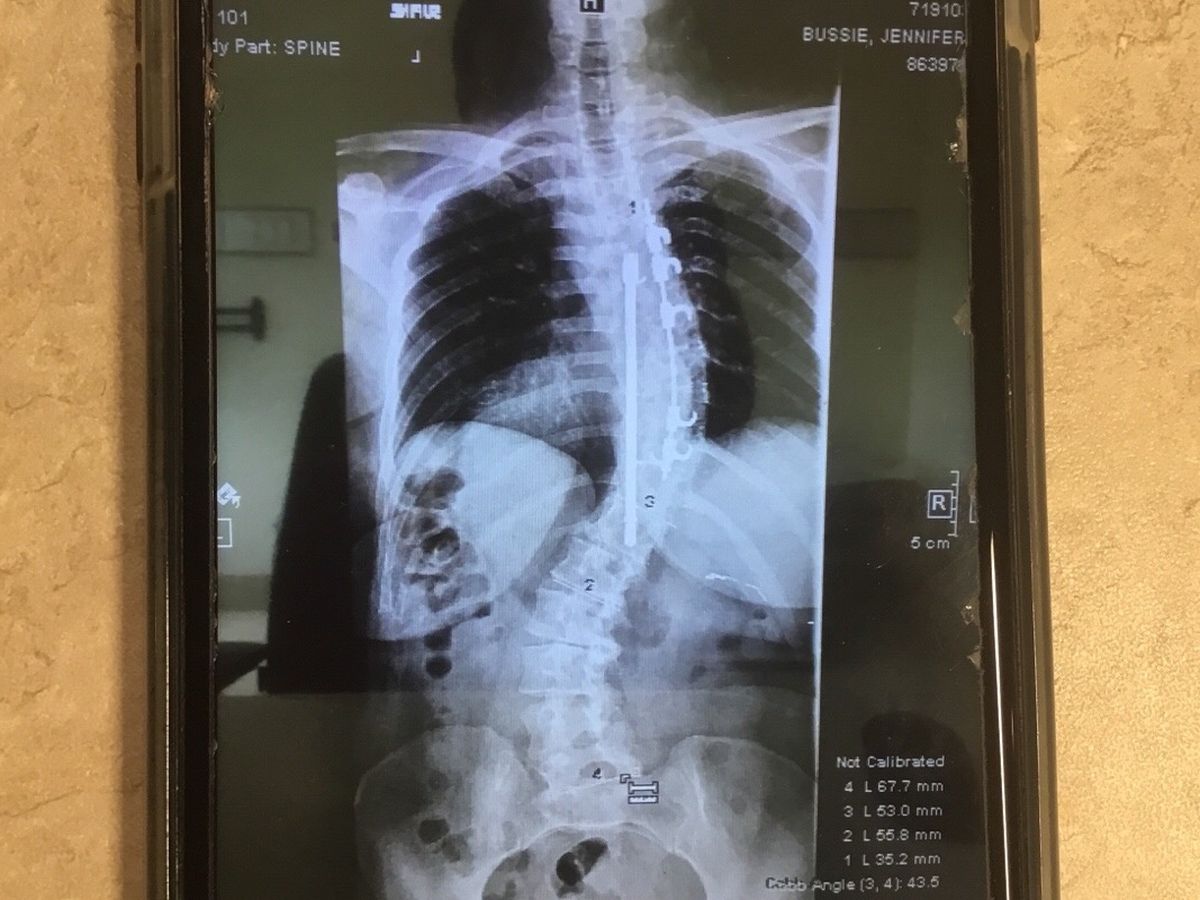

This photo is a current x-ray of the back of one of the most Godly, amazing, and loving women I know. She had her first scoliosis surgery 34 years ago, where they installed the hardware you can see in this photo. Over the last several years my friend has suffered from severe pain, numbness in her arm and hand and also loosing the feeling in her left foot. After much prayer and petition Jennifer and her husband Ted sought out the help of a doctor in NYC. This doctor hand picks his patients. After her first consult with this doctor, he picked Jen. Tomorrow 8/19/19, Jennifer will have all her old hardware removed and receive new hardware. She will be in ICU for a day or two then in a regular room for five days. After being discharged she has to stay at a nearby hotel for a week. With several follow up visits in the near future. This is where you come in. Ted and Jennifer are small business owners and when small business owners can’t work there’s no money coming. Theses trips from Alabama to NYC are very expensive with air fare, hotels, food, and transit systems in the city. They have thirteen children with five of them still small and living at home. Please be in prayer for all of them. If you can find it in your heart to donate too, I along with my amazing friends, will be forever grateful.